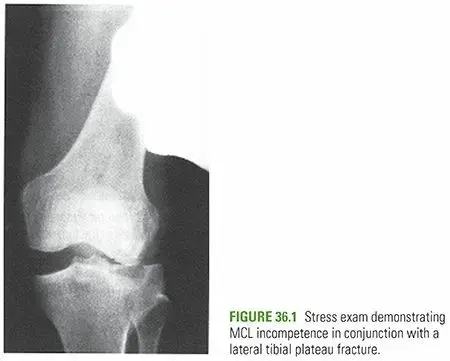

التصوير بالأشعة السينية (X-rays):

- هي الخطوة الأولى والأكثر شيوعًا لتأكيد وجود الكسر.

- تُؤخذ صور متعددة للركبة من زوايا مختلفة (أمامية، جانبية، مائلة) لتحديد موقع الكسر ونوعه ومدى تشرده.

- تُظهر الأشعة السينية صورًا للعظام بشكل جيد، لكنها قد لا تكشف دائمًا عن جميع تفاصيل الكسر أو إصابات الأنسجة الرخوة.